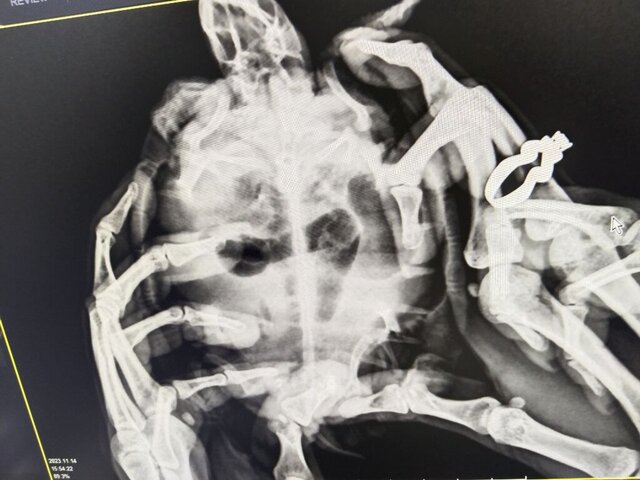

Константи Ваше имя: Константин Локация: Узбекистан Опубликовано: 14 ноября 2023 Автор Опубликовано: 14 ноября 2023 Сделали рентген, внутри ничего инородного они не увидели. Какие действия предпринять далее? Аппетит у черепахи отсутствует. Сейчас пробуем через пластиковый катетер прямым путем ввести еду. Не знаю правильно или нет. Что посоветуете делать?

Константи Ваше имя: Константин Локация: Узбекистан Опубликовано: 14 ноября 2023 Автор Опубликовано: 14 ноября 2023

Консультанты moth Ваше имя: Мария Локация: Москва Опубликовано: 14 ноября 2023 Консультанты Опубликовано: 14 ноября 2023 @Константи а вторую проекцию не делали? по этой проекции у неё газы и в желудке и в жкт

Константи Ваше имя: Константин Локация: Узбекистан Опубликовано: 15 ноября 2023 Автор Опубликовано: 15 ноября 2023 Нет, только так делали. У нас в Узбекистане специалистов вообще нет. Подскажите пожалуйста что делать?

Консультанты moth Ваше имя: Мария Локация: Москва Опубликовано: 15 ноября 2023 Консультанты Опубликовано: 15 ноября 2023 @Константи нужно выводить газы, у неё очень сильно раздут желудок и кишечник. Вот это тёмное на снимке - это всё раздутые кишки и желудок. Вам нужно купить Эспумизан и внутривенный катетер (попросите продать в любой ветклинике). Выпаивать зондом 0.02мл Эспумизана раз в сутки. Сколько дней черепаха не ест? если больше 10, то можно также зондом докармливать. Нужно Рептомин развести до состояния воды и выпоить 0.5мл для начала. Также добавьте вибротерапию - положите черепаху в небольшой контейнер без воды и поставьте на сильно вибрирующий прибор на 10 минут, можно на телефон в режиме максимальной вибрации. И 1-2 раза в день заставляйте плавать по аквариуму. Но следите за одышкой, если начнёт дышать ртом - оставить в покое. 1